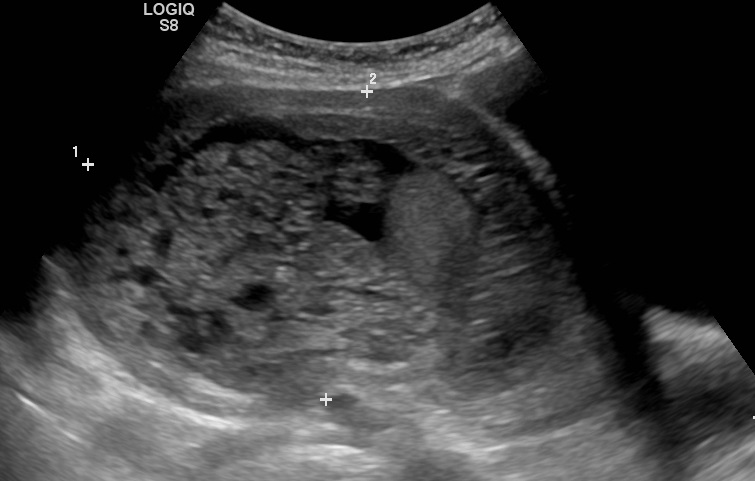

초음파 사진에서 기태는 포도송이("포도송이 떼", "벌집 자궁", "눈보라")와 유사하게 나타난다.[14] CT 촬영을 통해 자궁강 내에 과립상의 구조가 관찰된다.